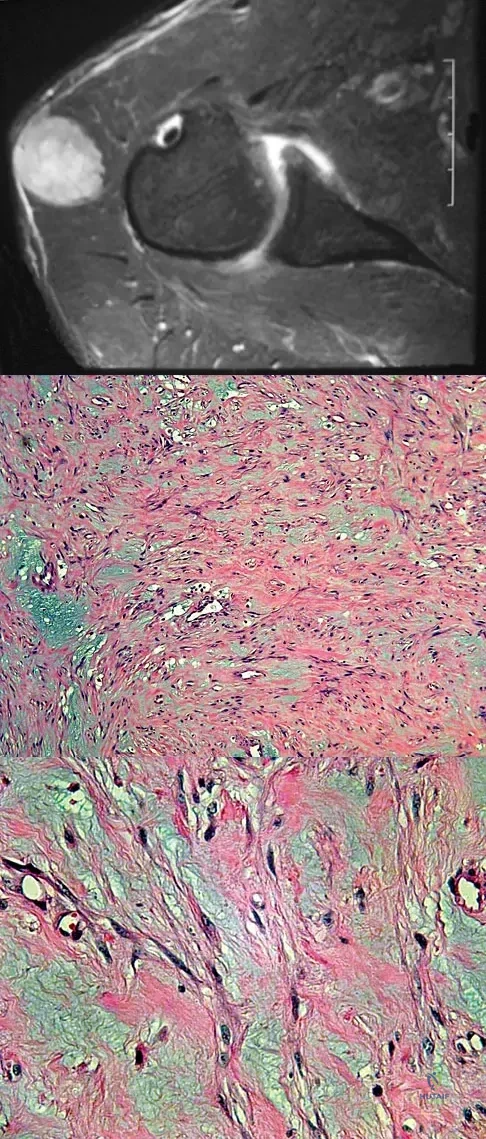

Question 16

A 40-year-old man reports an enlarging soft-tissue mass in his right shoulder. Based on the MRI scan and biopsy specimens shown in Figures 40a through 40c, what is the most likely diagnosis?

Explanation

A 28-year-old woman has left shoulder pain and a tender soft-tissue mass. Based on the MRI scan and biopsy specimens shown in Figures 74a through 74c, what is the most likely diagnosis?

Explanation